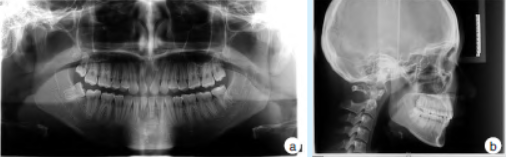

4. 治疗及结果

牙周基础治疗后行牙周骨成形术及牙龈成形术。术后2 周及2 个月复查无不适,12、22 牙龈色形质良好,形态正常,唇侧牙槽骨基本正常(图3)。术后半年复查显示12、22 间牙龈及牙槽骨形态稳定,未见增生复发(图4)。

图4 正畸治疗致12、22间唇侧骨性凸起牙周手术后半年全景曲面断层片及头颅侧位片